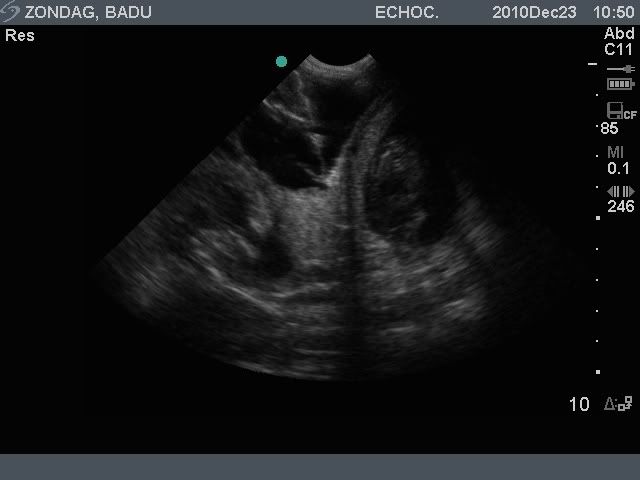

Vandaag zijn we voor een drachtecho geweest en…. we telden ongeveer 5 pups. Het aantal was niet helemaal goed te bepalen omdat mevrouw het een idioot plan vond om op haar rug te gaan liggen. Staand was het moeilijk tellen…